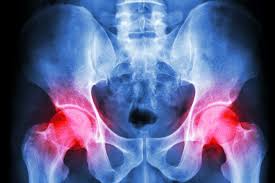

În timp ce osteoartrita poate afecta orice articulatie in corpul dumnavoastra mai ales la genunchiul si solduri. Proteze de dezarticulatie de umar.

In april, branson shed 0 million worth of his holdings, which was followed by cathie wood selling off 275,204 shares from her ark space exploration and innovation (bats: În cele ce urmează voi trece în revistă aceste două categorii astfel încât să aduc un pic de transparență în ceea ce privește modul în care medicul ortoped recomandă pacienților un. Adesea numit artrită de uzura, osteoartrita apare atunci când cartilajul se distrugere progresiv la nivelul soldului.